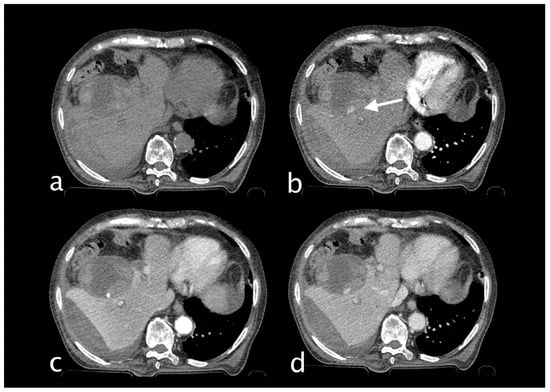

2. Imaging

3.1.3. Imaging and Diagnostic Findings